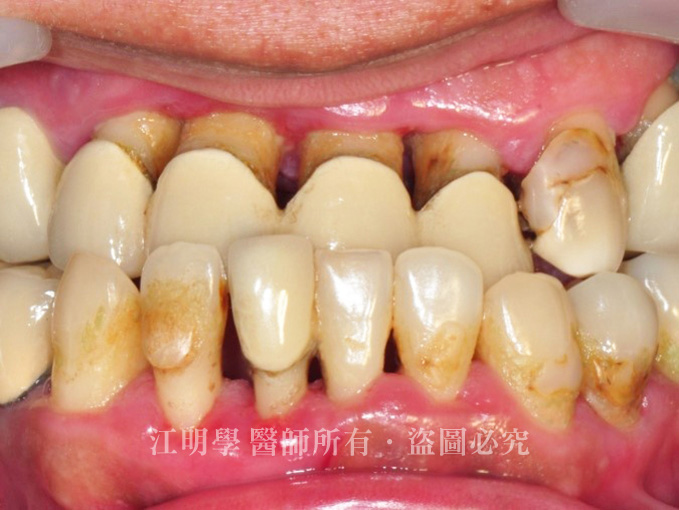

多年前製作的瓷牙套,因為使用已久,密合度不足,開始出現縫隙甚至脫落,已嚴重影響進食,長期飲食不均衡,直到去醫院健檢時發現健康亮起了紅燈,為了從根本解決問題,才下定決心來求診。

治療前:牙肉因剌激而萎縮,假牙逐漸脫落,且因清潔不易,口腔常常伴隨嚴重異味。